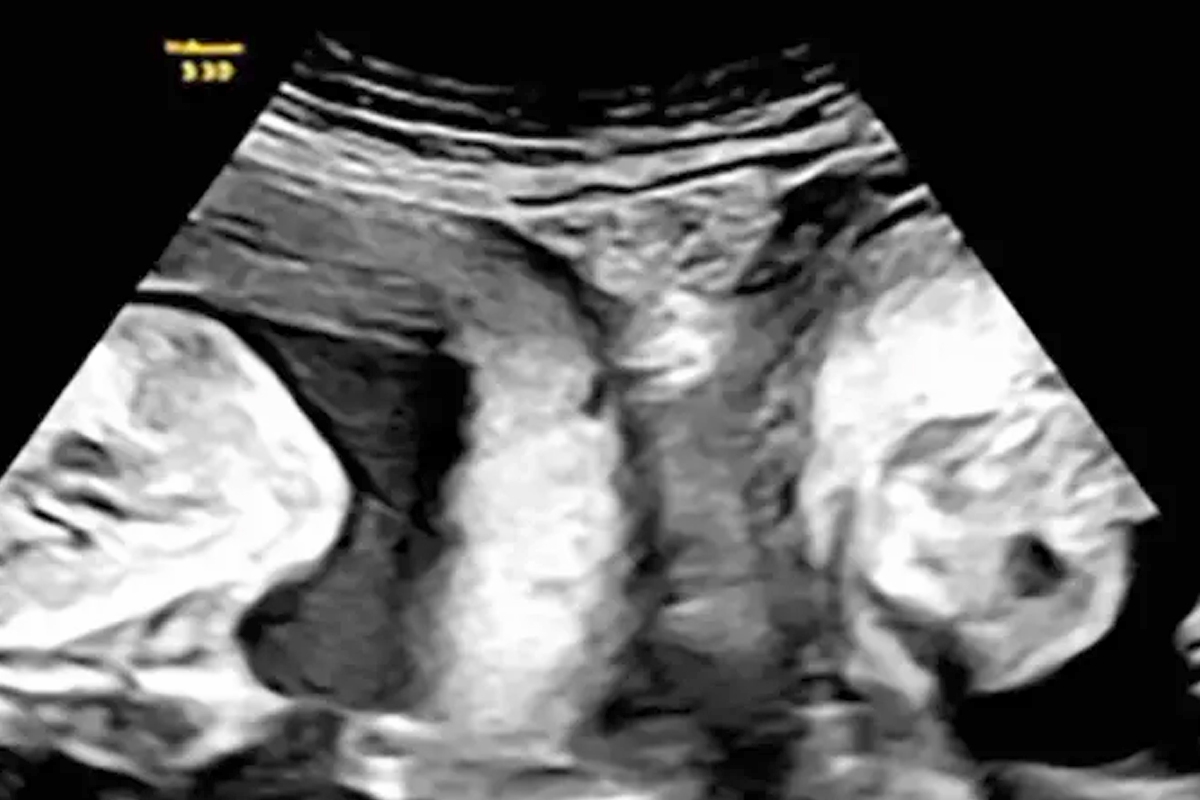

أنجبت امرأة تعاني حالة نادرة بامتلاكها «رحمين»، توأمين، واحد من كل رحم، في مستشفى بشمال غرب الصين.

وواجهت المرأة مصاعب لتتمكن من تحقيق حلم الأمومة، إذ كشف المستشفى أنها أجهضت في حمل سابق، لكن في يناير، حملت مرة أخرى، واكتشفت أثناء الموجات فوق الصوتية المبكرة أنها ستنجب طفلين (واحد من كل رحم).